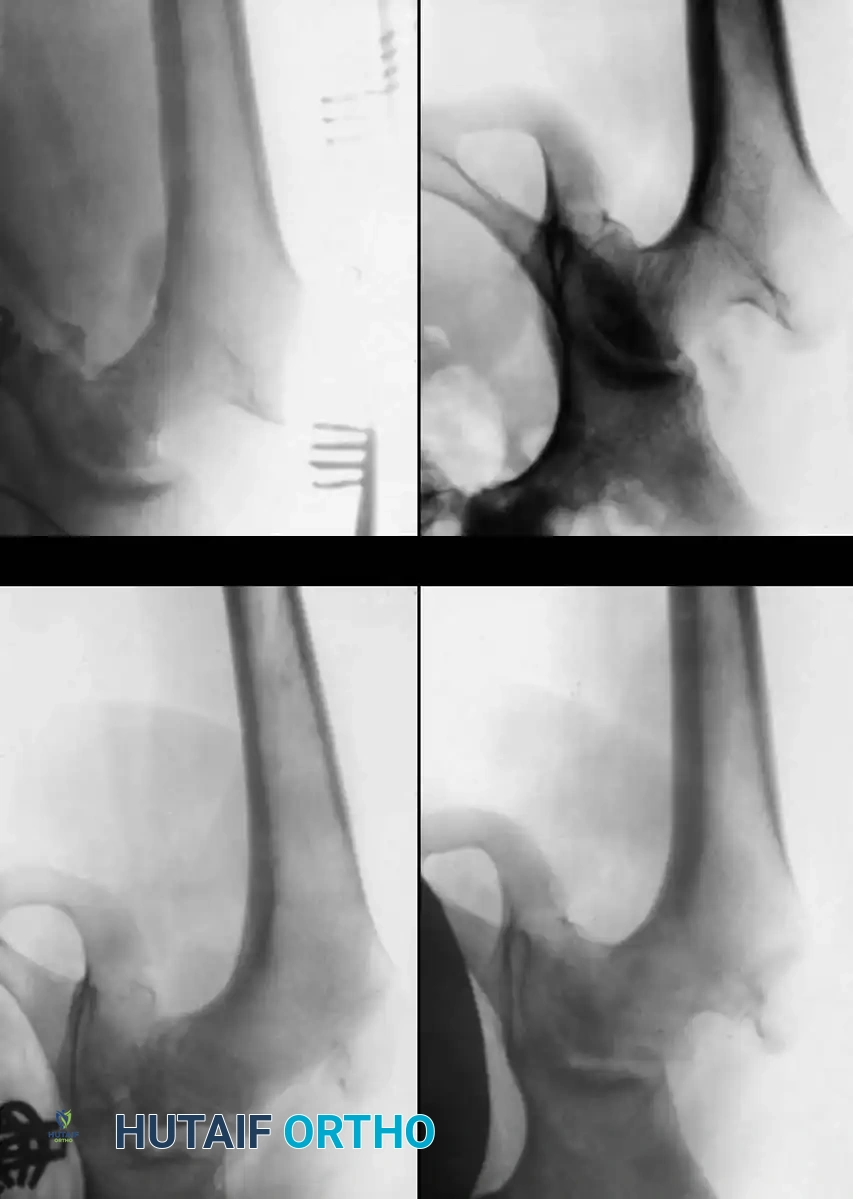

Salter and Thompson simplified early classification by measuring the extent of the subchondral fracture (crescent sign) in the superolateral femoral head on frog-leg lateral radiographs.

* Type A: Fracture line involves less than 50% of the superior dome (Good prognosis).

* Type B: Fracture line involves more than 50% of the superior dome (Fair/Poor prognosis, often requiring innominate osteotomy).

While Mukherjee and Fabry validated its accuracy, our institutional experience notes that subchondral fractures are visible early in only one-third of patients, limiting its universal application.

3. Guidewire Placement: Under strict fluoroscopic guidance, a guidewire is advanced into the femoral neck and head, parallel to the planned angle of the blade plate. The goal is typically to achieve a neck-shaft angle of 110 to 115 degrees.

4. Osteotomy: A transverse or closing-wedge osteotomy is performed at the intertrochanteric level using an oscillating saw.

5. Derotation and Varus: The distal fragment is externally rotated (typically 15-20 degrees) to correct the anteversion, and the proximal fragment is allowed to fall into varus.

6. Fixation: A pediatric locking plate or a fixed-angle blade plate is impacted into the proximal fragment and secured to the distal shaft with cortical screws. Compression is applied across the osteotomy site.